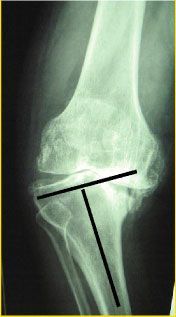

Mise au point Index de mesure de hauteur de la rotule , Jacques Caton Centre Hospitalier Saint-Joseph et Saint-Luc, 9 rue du Professeur Grignard, Lyon, France , Gérard Deschamps Centre de Chirurgie Orthopédique, 71640 Dracy le Fort, France N°103 - Avril 2001 ● 3 min de lecture